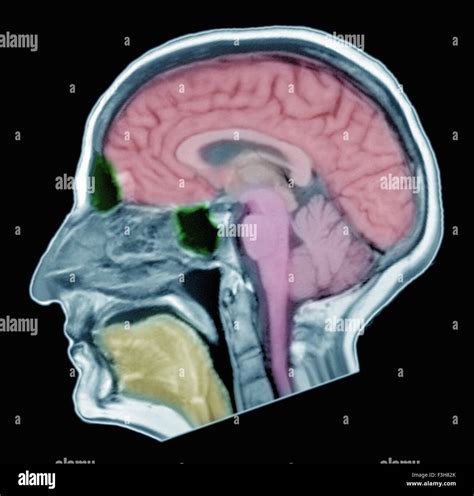

Receiving the results of a neurological examination can be an anxious experience, especially when waiting for clarity regarding your health. Understanding what constitutes a normal brain MRI is a critical step in demystifying the diagnostic process. A magnetic resonance imaging (MRI) scan of the brain is a non-invasive, painless procedure that uses magnetic fields and radio waves to create detailed, high-resolution images of the brain's structures. When a radiologist reviews these images and labels them as "normal," it signifies that the anatomy of the brain appears consistent with healthy, standard expectations for your age and demographic, with no evidence of major structural abnormalities, tumors, or lesions.

• Ventricular System: Examining the fluid-filled spaces of the brain to ensure they are the correct size and shape.

• White and Gray Matter: Ensuring the tissue density and distribution are consistent with healthy neural architecture.

• Brain Stem and Cerebellum: Checking for clear structures at the base of the brain responsible for vital functions.

• Major Blood Vessels: Assessing for signs of vascular abnormalities, such as aneurysms or stenoses.